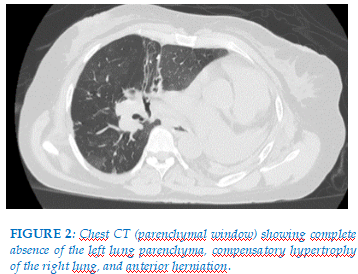

Lung ultrasound revealed no pleuro-pulmonary line and no pleural effusion, but cardiac chambers were visualized. Chest computed tomography demonstrated complete absence of left pulmonary parenchyma with compensatory hypertrophy of the right lung (Figure 2).

An abrupt termination of the left pulmonary artery, along with cardiac deviation and rotation, was also noted (Figure 3). Flexible bronchoscopy showed that immediately beyond the trachea, the airway continued directly into the right main bronchus. Histopathological examination of a biopsy from the bronchial spur between the upper and middle lobar bronchi, as well as cytological analysis of bronchoalveolar lavage, revealed no evidence of malignancy or infection. A diagnosis of pulmonary agenesis was established. Spirometry demonstrated a forced vital capacity (FVC) of 0.94 L (44% predicted), an FEV1/FVC ratio of 56.4% (82% predicted), and a pre-bronchodilator forced expiratory volume in one second (FEV1) of 530 mL (31% predicted). Post-bronchodilator FEV1, measured 15 minutes after four puffs of 100 μg salbutamol, increased to 750 mL (44% predicted). These findings indicated airflow obstruction with a post-bronchodilator FEV1 improvement of 220 mL (13%), and a probable associated restrictive ventilatory defect. Cardiac and abdominal ultrasound examinations did not reveal any associated malformations. Treatment with a combination of formoterol 6 μg and budesonide 200 μg was initiated.